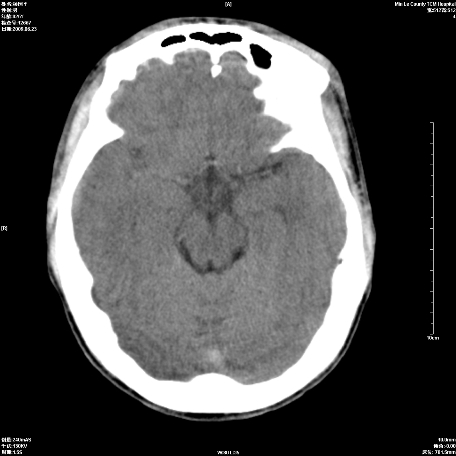

以下是引用zxl51642在2009-6-23 14:15:00的发言:[br]1、颅内未见血肿,颅骨未见骨折;[br]2、双侧苍白球对称性钙化,透明隔间腔及verga氏腔形成。